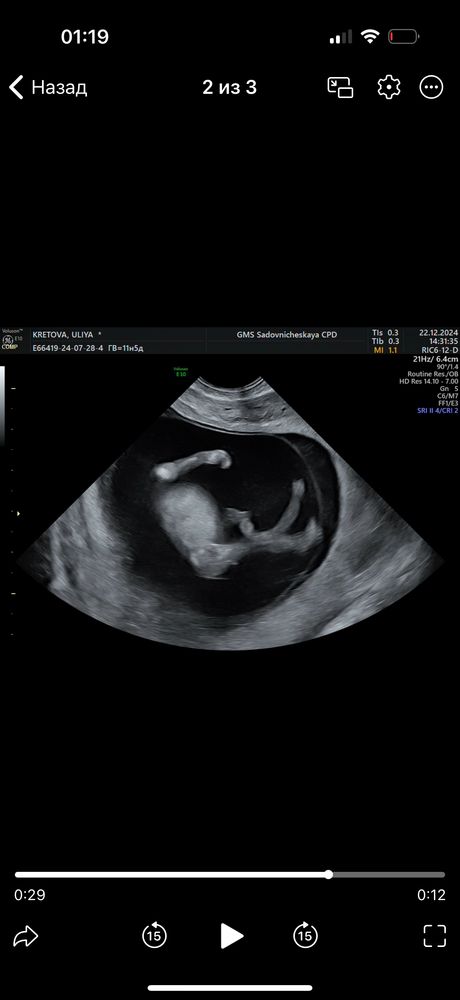

похоже девочку)) я была на узи в 15+4

на фотке было чуть не так (у нас был ракурс как на 2 фото и между ножек ничего не было вообще) но у меня 2 мальчика и я помню их на узи - там в таком ракурсе сомнений не было)))

Eva , здравствуйте, с первого только видео отправили в чб и 3д, но там ракурсы такие, что ничего не видно, к сожалению

19.01.2025